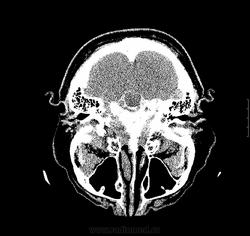

3.06.12 больному выполнена КТ без контраста, заподозрено подкравливание из аневризмы бифуркации базилярной артерии, либо ее тромбирование. Рекомендовано проведение СКТ-АГ.

04.06.2012 проведено СКТ-АГ, выявлено объемное образование ската, спинки турецкого седла с супраселлярным  ростом. Небольшое неоднородное накопление контраста в строме опухоли.

так аневризма то есть или нет? за опухоль наверное могли принять сгусток в предмостовой цистерне, сигнал на Т1 с контрастом и без от предмостовой цистерны одинаков на мой взгляд. МРТ контроль в динамике решит вопрос ИМХО.

Я извиняюсь-может быть, не в тему,но мне интересно  на представленных сканах МР(КТ) признаки внутричерепной гипертензии найти.Просто недавно  разбирали эту тему, поэтому сейчас обращаю  внимание на все,включая форму глазных яблок и состояние зрительных нервов, не говоря уже про узость боковых желудочков ( здесь кроме незаращения лисков прозрачной перегородки, желудочки в норме).Согласна с Евгением по поводу признаков наличия крови ( недавно случай выставлялся,кажется, Евгением Широковым).